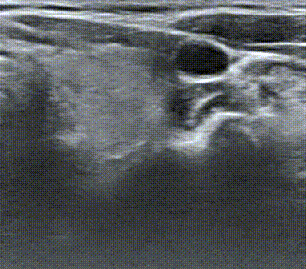

主诊医生、深圳市人民医院甲乳外科医生王元阳看完后,觉得很可疑,就给大姐的可疑结节再做了个“细针穿刺”——这是目前国际和国内甲状腺领域在术前进行诊断的金标准,用于鉴别甲状腺结节是恶性还是良性。

“如果穿刺结果是良性,我们会建议患者每6个月复查一次彩超,来追踪形态的变化;

如果是恶性的,相当于我们在术前,已经知道甲癌诊断,术中就可以直接按照甲癌的方式进行根治性手术,并大幅缩短冰冻病理等待时间,冰冻化验变成了术中印证细胞学的一个双保险,至少能缩短30分钟的手术时间。

而良性结果的结节,也让患者免除多挨一刀的冤枉,避免过度治疗。”王元阳说。